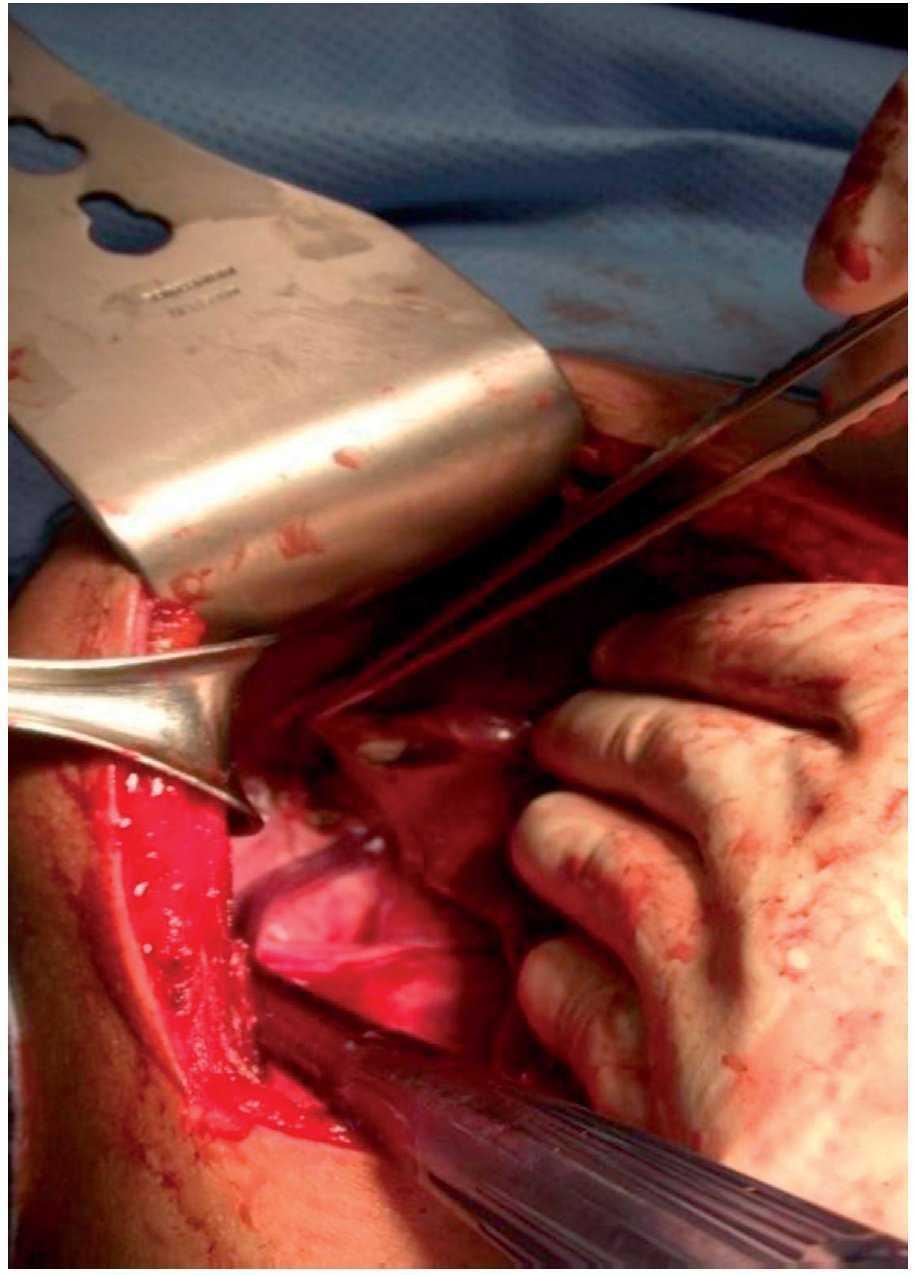

A right subcostal laparotomy was done at this precise location, to directly puncture the cyst, extracting a clear fluid that was sent to the pathologist. When the upper portion of the capsule was removed, the window created showed that the cyst was different from a simple biliary cyst of the liver because it had a second layer formed by whitish tissue (Fig. 2), completely covering the interior of the cyst. This second layer was removed in its entirety after the rest of the abdomen was isolated using surgical compresses and the cavity of the cyst was impregnated with hypertonic saline solution by means of a compress left inside it for 10 minutes. The procedure was completed with a pedicled greater omentum omentoplasty.

Figure 2. The liver reclined with the hand to the left of the patient. The whitish layer of the germinal membrane is visible.